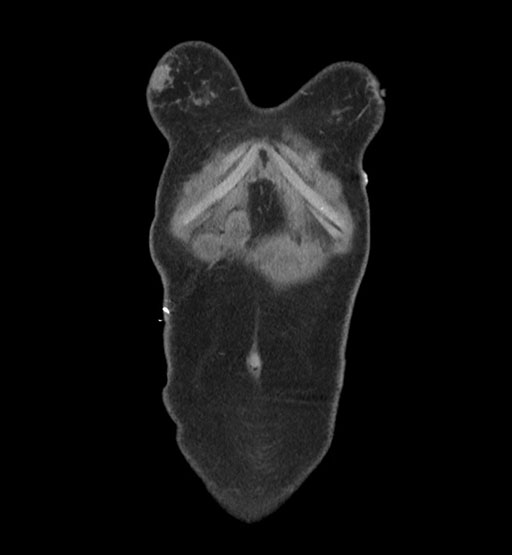

MRI T1

MRI T2